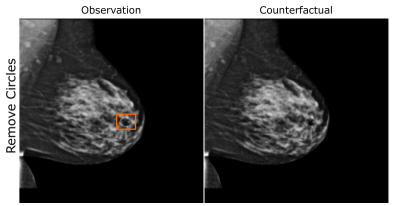

EMBED

Using prior insights, we apply our mechanisms to a real-world artefact removal task on the EMory BrEast imaging Dataset (EMBED) (Jeong et al., 2022). Schueppert et al. (2024) observe that triangular and circular skin markers are spuriously associated with breast cancer in classifiers due to shortcut learning (Geirhos et al., 2020), and manually labelled 22,012 affected mammograms. Using this dataset, we train a significantly scaled-up, amortised, anti-causally guided semantic mechanism () to remove skin markers. We model triangular markers (), circular markers (), breast density (), and cancer () as independent parents of the mammogram , and remove artefacts by intervening on and while holding and fixed. Figure 6 shows that our mechanisms effectively remove artefacts and can disentangle representations for triangles and circles. We successfully remove of triangles and of circles in our test set - a noteworthy result given the dataset’s small size and the scarcity of labelled skin markers (Appendix I).